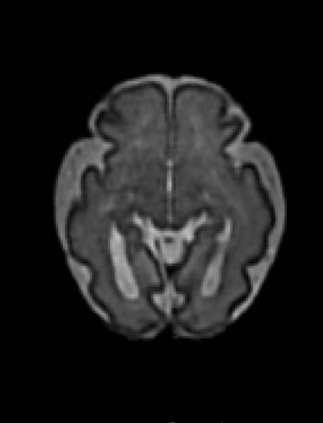

Fetal cortical plate segmentation is essential in quantitative analysis of fetal brain maturation and cortical folding. Manual segmentation of the cortical plate, or manual refinement of automatic segmentations is tedious and time-consuming. Automatic segmentation of the cortical plate, on the other hand, is challenged by the relatively low resolution of the reconstructed fetal brain MRI scans compared to the thin structure of the cortical plate, partial voluming, and the wide range of variations in the morphology of the cortical plate as the brain matures during gestation. To reduce the burden of manual refinement of segmentations, we have developed a new and powerful deep learning segmentation method. Our method exploits new deep attentive modules with mixed kernel convolutions within a fully convolutional neural network architecture that utilizes deep supervision and residual connections. We evaluated our method quantitatively based on several performance measures and expert evaluations. Results show that our method outperforms several state-of-the-art deep models for segmentation, as well as a state-of-the-art multi-atlas segmentation technique. We achieved average Dice similarity coefficient of 0.87, average Hausdorff distance of 0.96 mm, and average symmetric surface difference of 0.28 mm on reconstructed fetal brain MRI scans of fetuses scanned in the gestational age range of 16 to 39 weeks. With a computation time of less than 1 minute per fetal brain, our method can facilitate and accelerate large-scale studies on normal and altered fetal brain cortical maturation and folding.